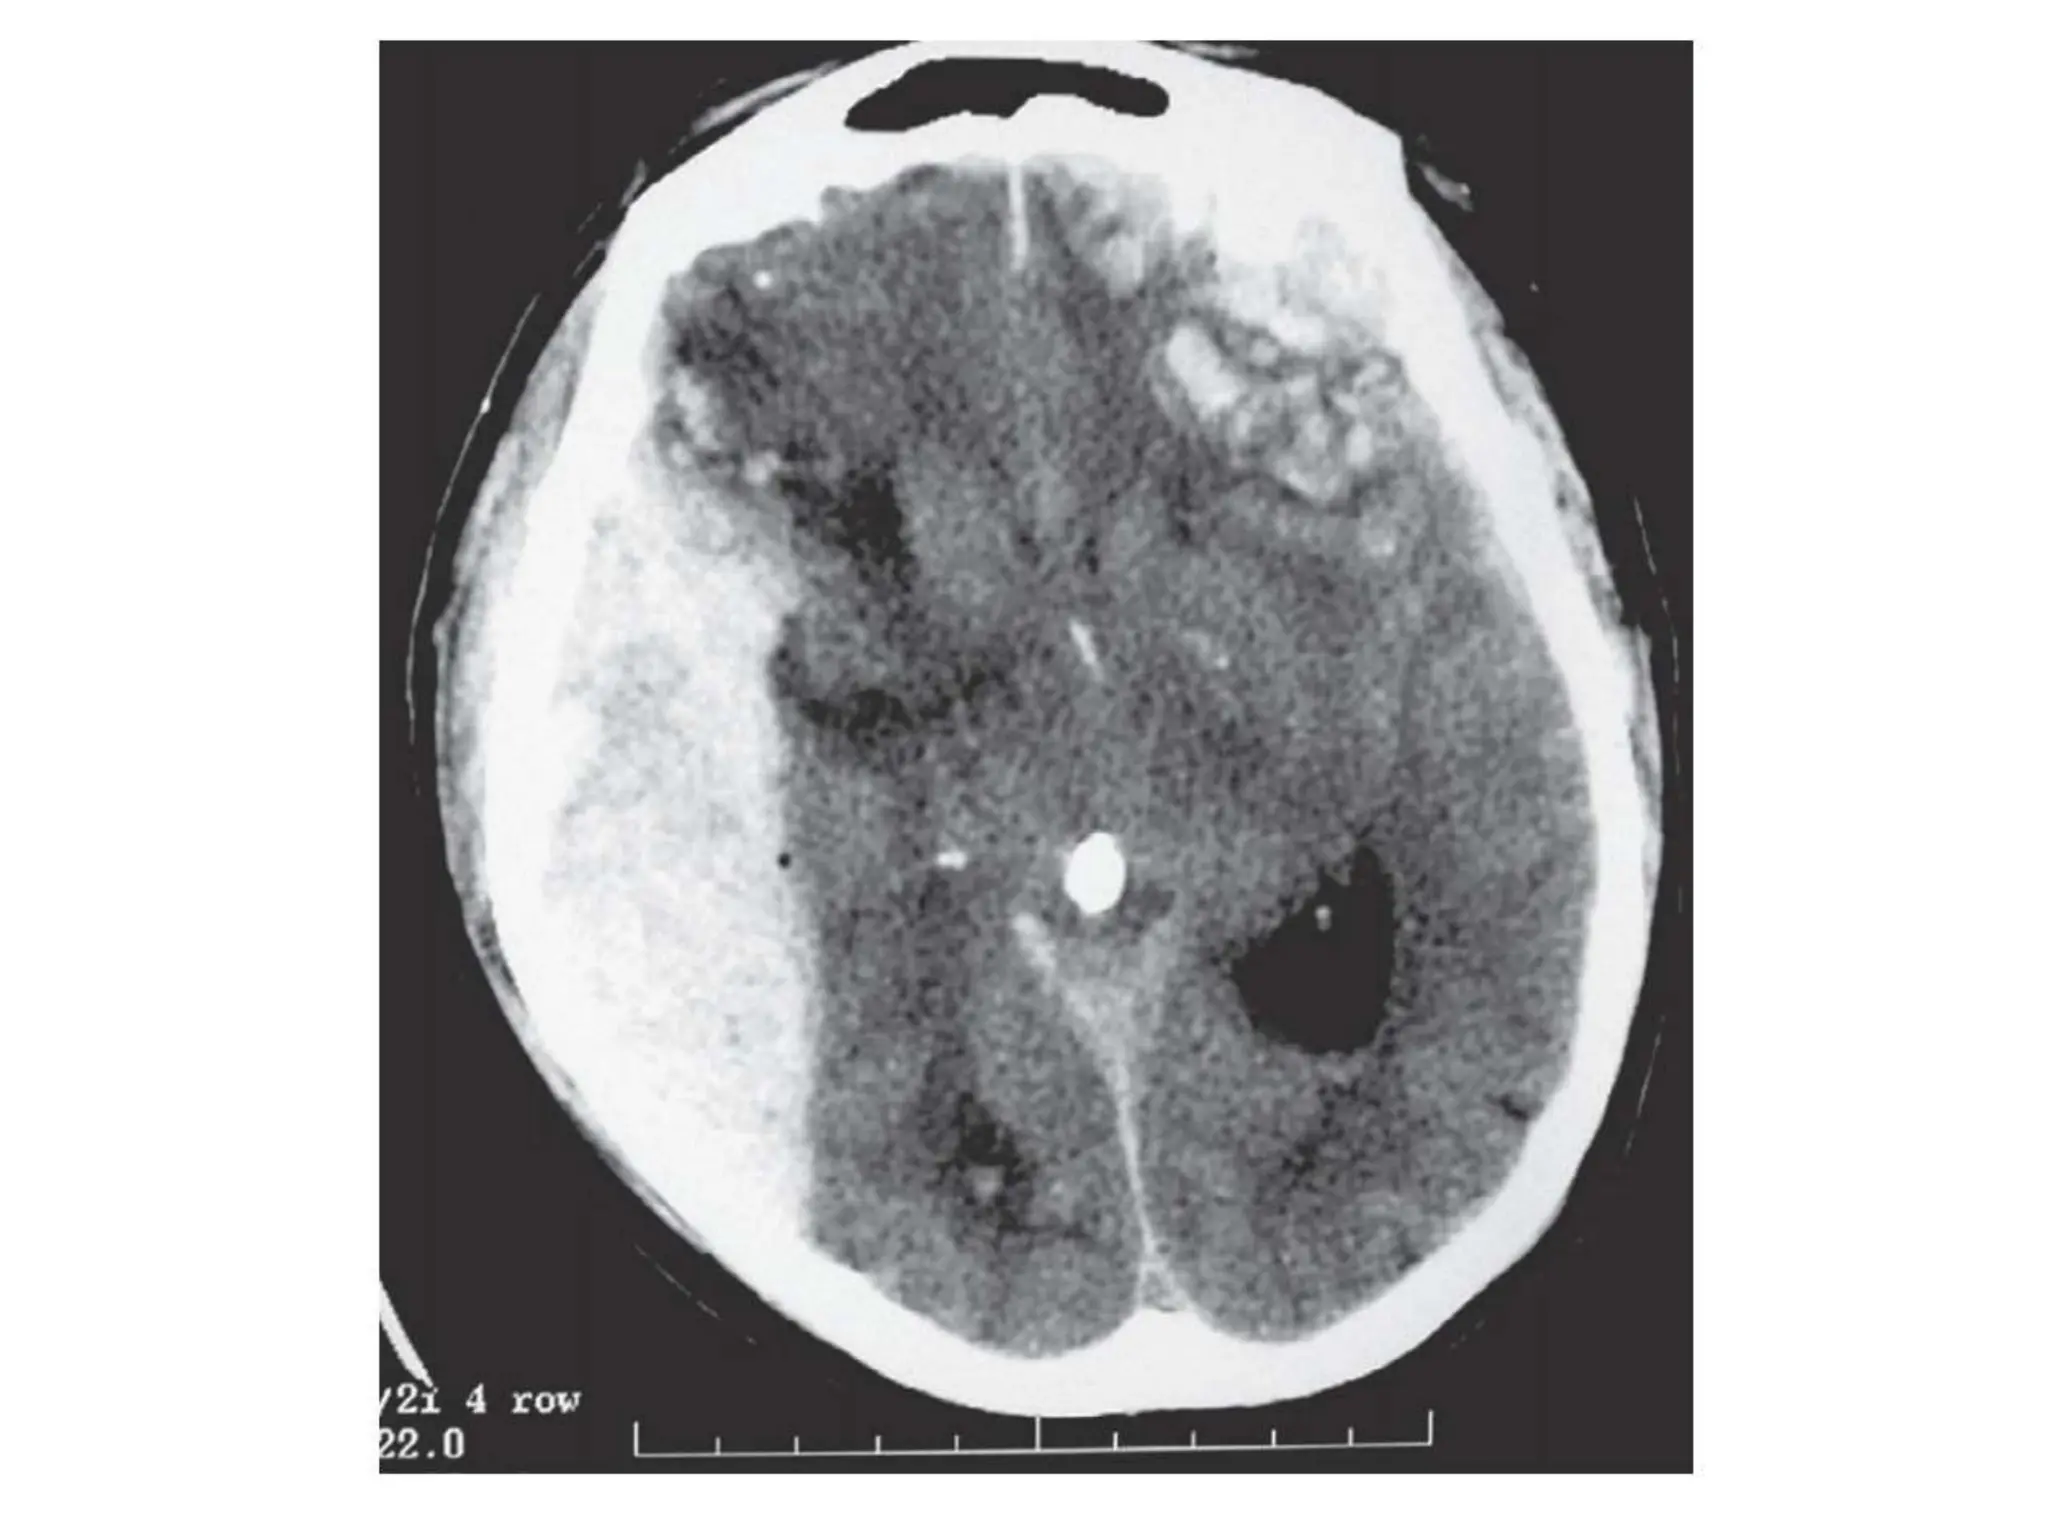

Cerebral contusion

• Contusions are common and are found predominantly

where

• the brain is in contact with the irregularly ridged inside

of

• the skull, i.e. at the inferior frontal lobes and temporal

poles.

• ‘Coup contre-coup’ contusions refer to brain injury

both at

• the site of impact and distant to this, where the brain

impacts

• on the inside of the skull as the skull and brain

accelerate and

• then decelerate out of synchrony with each other.

Cerebral contusion • Contusionsare common and are found predominantly where • the brain is in contact with the irregularly ridged inside of • the skull, i.e. at the inferior frontal lobes and temporal poles. • ‘Coup contre-coup’ contusions refer to brain injury both at • the site of impact and distant to this, where the brain impacts • on the inside of the skull as the skull and brain accelerate and • then decelerate out of synchrony with each other.